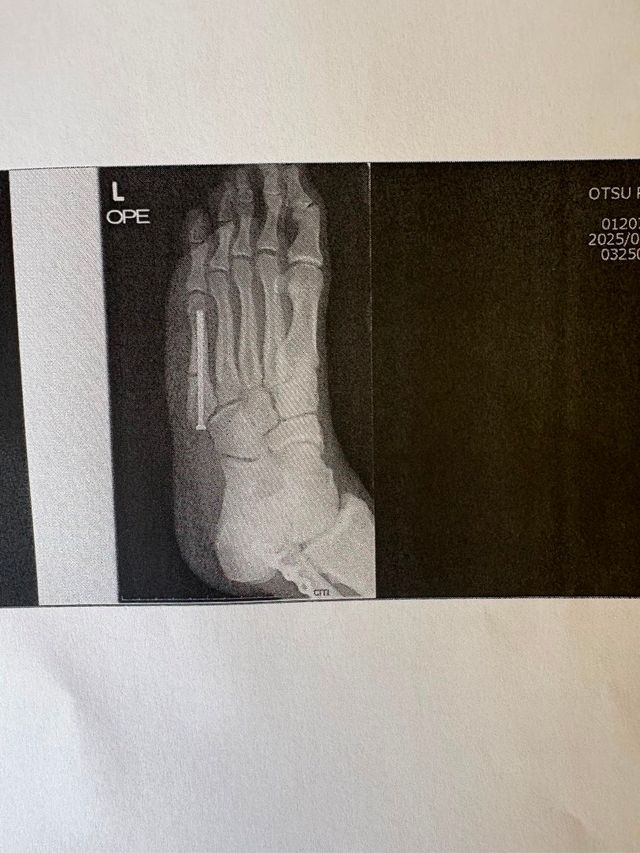

ちょうど中足骨のボルトと、腓骨のプレートが映ってます☝️

その他に肩に2本ボルト☝️

左前腕は3回手術してプレート除去済み

レギュラーに定着するも、練習時にアフタータックルを受けて左中足骨骨折

全体のBチーム所属、控えのボランチで秋頃、左足骨折でシーズン終了